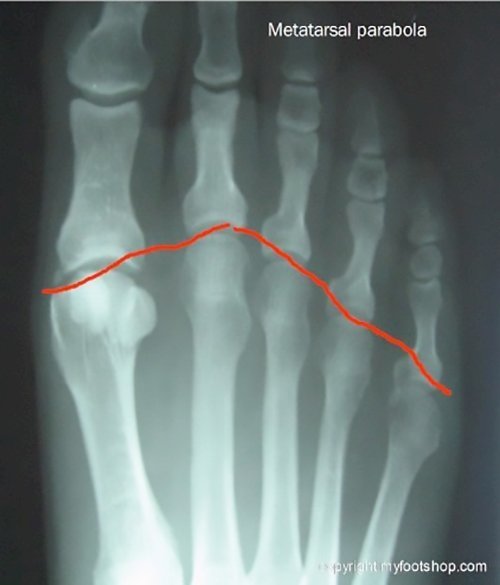

There are five metatarsal bones in each foot. The metatarsal bones descend from the midfoot to the ball-of-the-foot. The relative length of each metatarsal is important in creating the weight-bearing surface of the ball-of-the-foot. The image to the right shows the relative length of the metatarsals, often referred to as the metatarsal parabola. The importance of the metatarsal parabola is that it enables the foot to work as a unit, with no one metatarsal bearing more weight than any of the other metatarsals. When one metatarsal functions outside of the unit (outside of the function of the metatarsal parabola), that's when metatarsal transfer lesions may occur.

When the weight-bearing pattern of the metatarsal parabola is altered by surgery or trauma, the area where load b

ecomes focused is called a transfer lesion. Transfer lesions may occur following bunion surgery. In this case, the transfer lesion is found beneath the second metatarsal head. The cause of the transfer lesion is due to a decrease in the load-bearing capacity of the first metatarsal. Bunion surgery often requires a metatarsal osteotomy, or break in the metatarsal. If the first metatarsal heals in an elevated position, that elevated position will alter the load-bearing of the metatarsal parabola and cause a transfer lesion beneath the second metatarsal head.